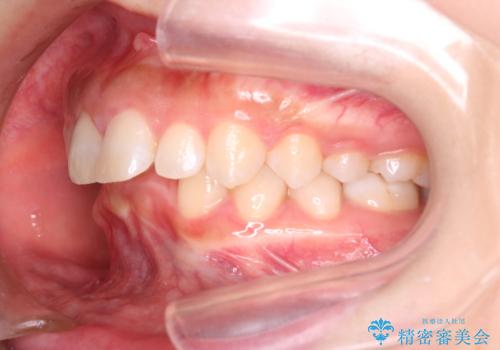

- 上の前歯の出っ歯と前歯の深い咬み合わせを治したいとのことで来院された患者様です。

上顎の歯は後方移動とIPR(歯と歯の間を削る)によって口元が引っ込むように、下顎は歯列全体の拡大とIPRによって上顎とバランスよく咬み合うように設計し、インビザラインにより治療を行うこととしました。

上顎歯列の後方への移動量が多く、右側の奥歯の咬み合わせを改善する必要もあったため、治療には長期間を要しました。